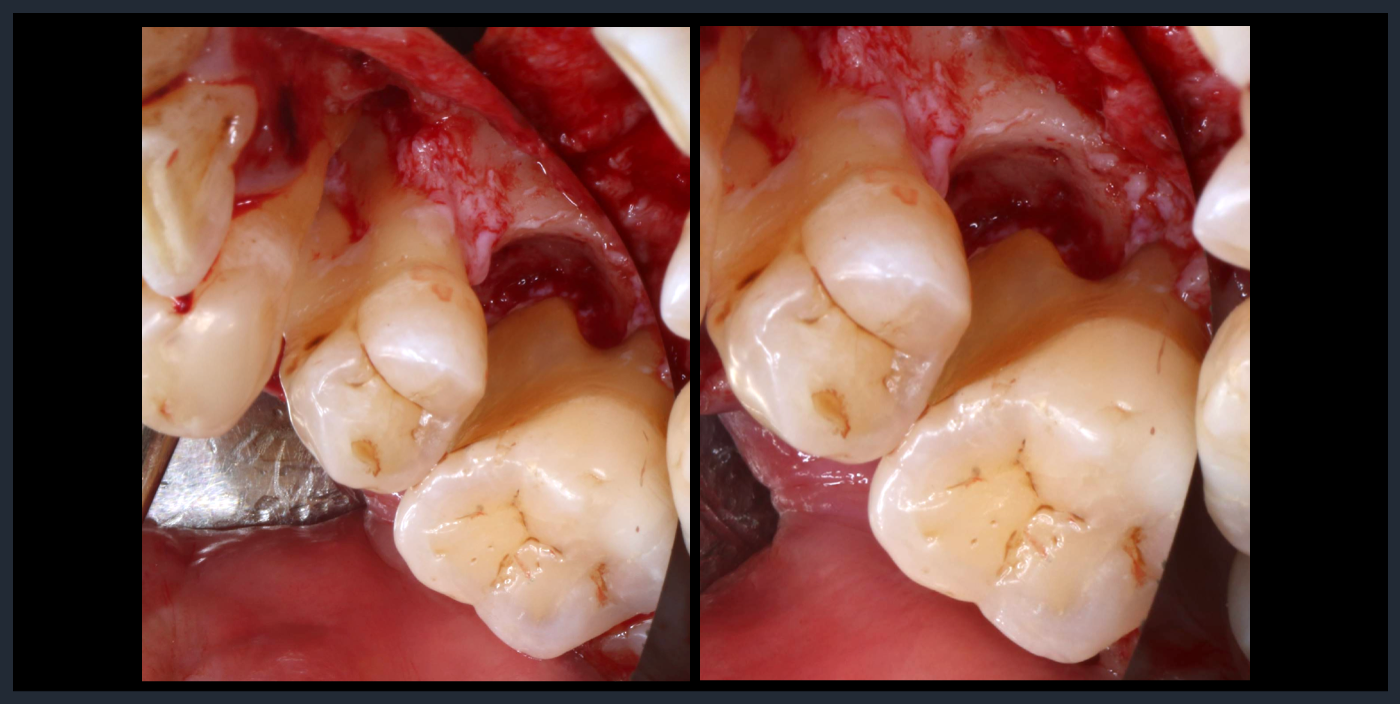

歯周組織再生療法

Periodontal tissue regeneration therapy

Periodontal tissue regeneration therapy

縁下歯石除去後。

歯周組織再生療法

Periodontal tissue regeneration therapy

Periodontal tissue regeneration therapy

縁下歯石除去後。

歯周組織再生療法

Periodontal tissue regeneration therapy

Periodontal tissue regeneration therapy

縁下歯石除去後。